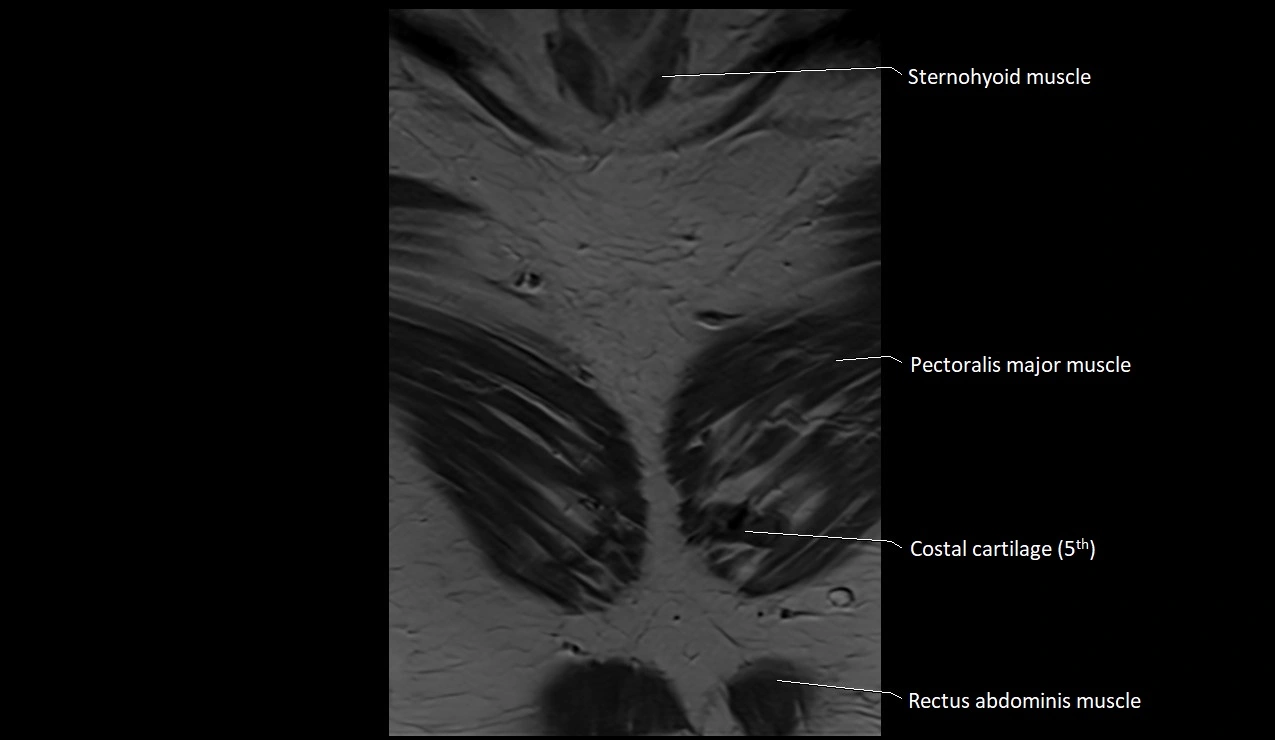

MRI images

image